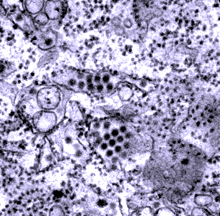

Round dengue virus particles revealed in a tissue specimen. Image courtesy of CDC.